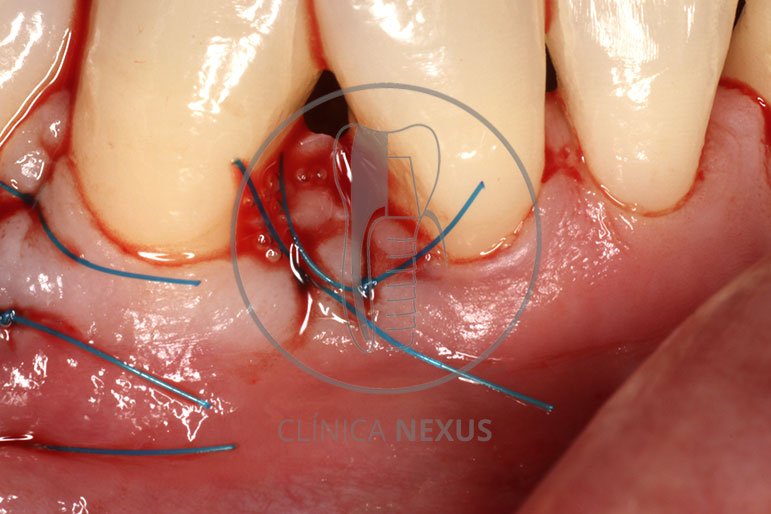

Tratamiento de defectos periodontales infraóseos en sector antero-inferior empleando gel de amelogeninas (Emdogain®) en combinación con un aloinjerto óseo (Biobank®). Paciente de 64 años, sin problemas médicos de relevancia, que presenta una periodontitis leve generalizada, pero asociada a presencia de defectos óseos verticales profundos a nivel de los espacios interdentales entre los caninos y los incisivos laterales inferiores. Tras la pertinente fase higiénica, se llevó a cabo una cirugía periodontal regenerativa, en la que, tras eliminar el cálculo subgingival (factor causal), se empleó una combinación de amelogeninas con un aloinjerto, para promover la regeneración tisular del periodonto perdido. Las imágenes clínicas y radiológicas, al año de seguimiento, reflejan un resultado terapéutico óptimo, con regeneración completa del tejido periodontal y mejora del pronóstico de los dientes involucrados.